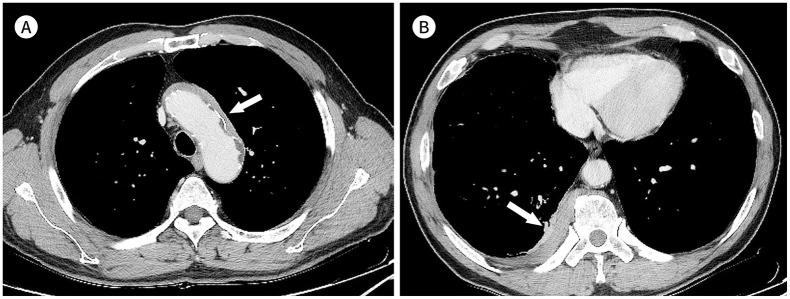

Immunoglobulin G4-related disease (IgG4-RD) is a chronic inflammatory condition involving multiple organs, including the salivary or lacrimal glands, orbit, pancreas, bile duct, liver, kidney, retroperitoneum, aorta, lung, and lymph nodes. It is histologically characterized by tissue infiltration with lymphocytes and IgG4-secreting plasma cells, storiform fibrosis, and obliterative phlebitis. In the thoracic involvement of IgG4-RD, mediastinal lymphadenopathy and perilymphangitic interstitial thickening of the lung are the most common findings. Peribronchovascular and septal thickening and paravertebral band-like soft tissue are characteristic findings of IgG4-RD. Other findings include pulmonary nodules or masses, ground-glass opacity, alveolar interstitial thickening, pleural effusion or thickening, mass in the chest wall or mediastinum, and arteritis involving the aorta and coronary artery. Radiologic differential diagnosis of various malignancies, infections, and inflammatory conditions is needed. In this review, we describe the imaging findings of IgG4-RD and the radiologic differential diagnoses in the thorax.

免疫球蛋白G4相关性疾病(IgG4-RD)是一种累及多个器官的慢性炎症性疾病,这些器官包括唾液腺或泪腺、眼眶、胰腺、胆管、肝脏、肾脏、腹膜后、主动脉、肺和淋巴结。其组织学特征为淋巴细胞和分泌IgG4的浆细胞浸润组织、席纹状纤维化和闭塞性静脉炎。在IgG4-RD累及胸部时,纵隔淋巴结肿大和肺淋巴管周围间质增厚是最常见的表现。支气管血管周围和小叶间隔增厚以及椎旁带状软组织是IgG4-RD的特征性表现。其他表现包括肺结节或肿块、磨玻璃影、肺泡间质增厚、胸腔积液或增厚、胸壁或纵隔肿块以及累及主动脉和冠状动脉的动脉炎。需要对各种恶性肿瘤、感染和炎症性疾病进行影像学鉴别诊断。在本综述中,我们描述了IgG4-RD的影像学表现以及胸部的影像学鉴别诊断。